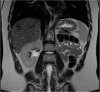

Introduction: Herlyn-Werner-Wunderlich syndrome (HWWS), also known as OHVIRA syndrome, is a rare congenital abnormality of Müllerian duct development characterized by uterus didelphys, unilateral blind hemivagina, and ipsilateral renal agenesis.

Presentation of case: In this report, the authors present the case of a 12-year-old patient presenting with progressive and disabling abdominal pain after the onset of menarche diagnosed with HWWS, describe the various diagnostic modalities and treatment options available, along with a current review of the literature.

Discussion: With normal external genitalia, HWWS is usually asymptomatic until menarche when patients present with worsening abdominal pain during menses and a palpable pelvic or abdominal mass. Untreated, HWWS may lead to a number of complications including endometriosis, infertility, and spontaneous abortion.